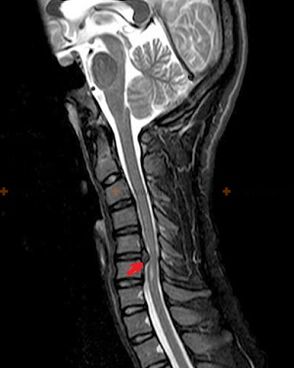

Diagnóstico y signos radiológicos.

La osteocondrosis es un diagnóstico por rayos X, ya que un cuadro clínico detallado está disponible solo en el momento de la exacerbación, mientras que los cambios en la columna pueden ocurrir con el completo bienestar subjetivo de una persona. Sin un examen de rayos X, solo podemos hablar de sospecha de osteocondrosis, porque síntomas similares pueden ser causados por otras enfermedades (miositis, neoplasias vertebrales y otras).

Para diagnosticar la osteocondrosis se utilizan los siguientes métodos de investigación: radiografía (preferiblemente con pruebas funcionales), MSCT y MRI. Este último estudio es preferible porque permite visualizar muy claramente el estado de las estructuras intervertebrales.

Los signos radiológicos de osteocondrosis incluyen los siguientes cambios en la columna:

- Altura reducida de los discos intervertebrales.

- Presencia de crecimientos óseos marginales.

- Violación de la ubicación de las vértebras entre sí.

- Deformaciones de cuerpos vertebrales y arcos, etc.

La presencia de los cambios descritos anteriormente, así como los cambios en la estructura del disco intervertebral, detectados mediante MSCT y MRI, sirven como signos confiables que confirman la presencia de osteocondrosis.